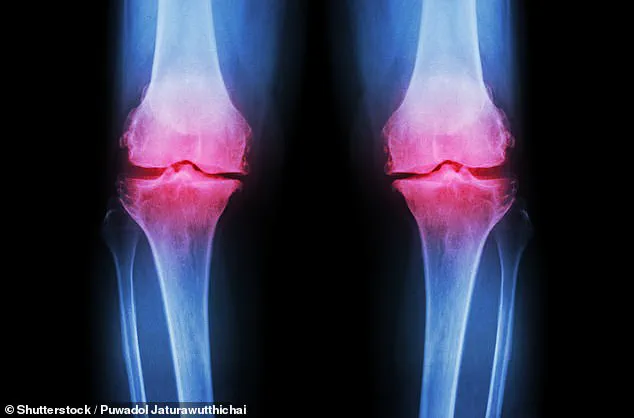

Over time, the erosion of cartilage results in bone-on-bone contact, causing pain, swelling, and joint deformity.

These symptoms not only diminish quality of life but also increase the risk of developing osteoarthritis, a degenerative condition that affects nearly 10 million Britons.

Osteoarthritis, a degenerative condition where cartilage erodes to the point that bones grind against each other, is notoriously painful and debilitating.

Mice treated with the protein inhibitor twice weekly for four weeks after injury showed significantly reduced signs of the disease.

In contrast, mice given a control treatment developed full-blown osteoarthritis within just four weeks, underscoring the inhibitor's potential to halt or even reverse the disease's progression.